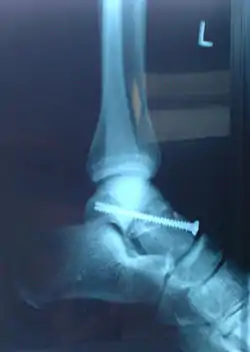

|   Imagerie d'une fracture de l'astragale, évènement-clé du roman. | ||||||||

En sautant d'un mur pour s'échapper de prison, Anne se brise l'astragale, un petit os du tarse. Elle se traîne sur le bord de la route nationale, hèle un poids lourd. L'homme, qui a peur des responsabilités, ne prend pas en charge Anne mais stoppe pour elle une voiture. Son conducteur, Julien, est lui aussi un repris de justice.